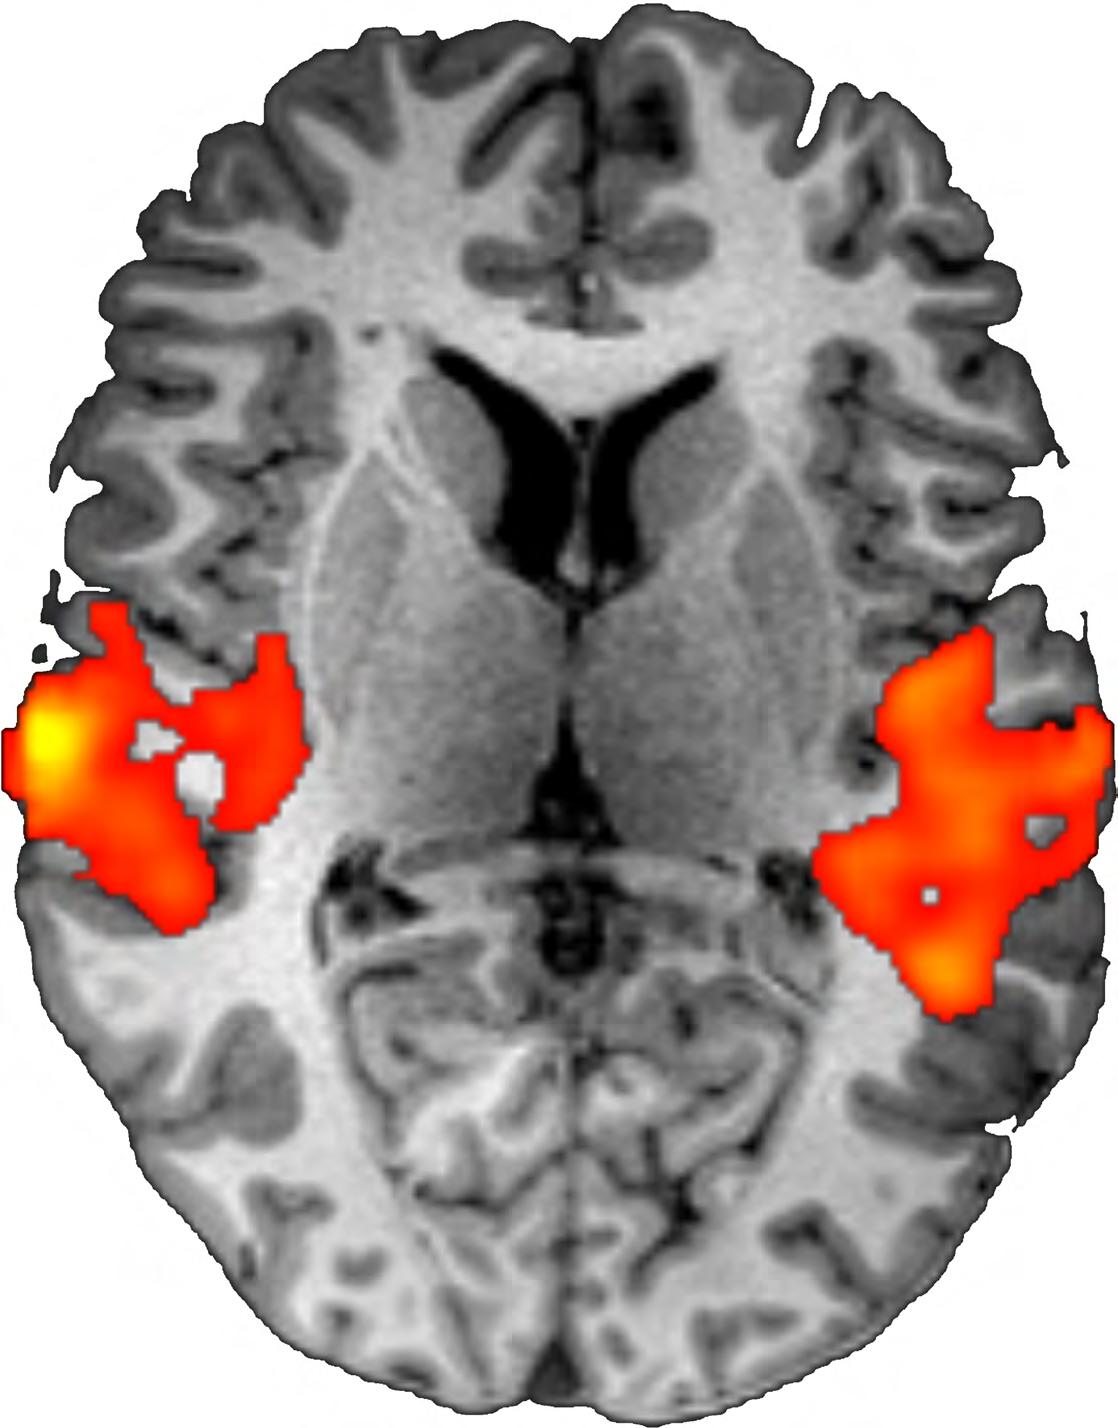

The introduction of functional MRI spurred researchers everywhere to adopt the technique for a range of applications. Among the early adopters, of course, were researchers at the Martinos Center. In the immediate wake of the Belliveau and Kwong papers in late 1991 and early 1992, respectively, Center investigators started using fMRI to address a host of questions the answers to which had long eluded them. Countless other applications followed, including explorations of the mechanisms underlying a number of human behaviors. Taken together, the findings of these studies have begun to circumscribe the heretofore entirely esoteric question of what it is that makes us who we are.